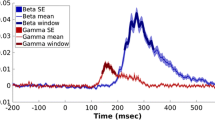

A negative association was found between BOLD response in the right inferior frontal gyrus (IFG) and middle frontal gyrus (MFG) and AQ percent score during laughter processing (see Fig. 1). A corresponding left hemispheric IFG/MFG cluster showed reduced activation in the ASD group in the between groups approach (see Supplementary neuroimaging results). No attribution or task-related effects were found in relation to AQ percent scores. Independently of AQ scores, more positive attributions were associated with increased BOLD signal in the ventral anterior cingulate cortex (see Supplementary neuroimaging results).

Association of BOLD response during laughter processing with AQ percent scores. A negative correlation was found between AQ percent scores and BOLD signal in the right inferior and middle frontal gyrus; i.e. activation during laughter processing in this cluster was reduced with increasing autistic traits. MNI peak coordinates: x = 42, y = 60, z = 6; tpeak = 5.44, pFWE; cluster size k = 156 voxels; pFWE = 0.008. Whole-brain statistical thresholding at p < 0.001, uncorrected at voxel level; FWE corrected for multiple comparisons at cluster level p < 0.05

Connectivity alteration during laughter processing

During overall laughter processing, reduced connectivity was found with increasing autistic traits between the left FFA and left IFG (Fig. 2a and Table 2). Further reduced connectivity with increasing AQ scores was found from the right FFA to multiple brain regions, including bilateral IFG, bilateral inferior parietal lobe, mid-cingulate cortex, and precuneus (Fig. 2b and Table 2). Corresponding between-groups analyses showed reduced connectivity in the ASD group between the right FFA and bilateral IFG/MFG as well as bilateral inferior parietal lobe (see Supplementary neuroimaging results). Altered connectivity from the remaining seeds as well as attribution and task-related connectivity alterations in relation to the degree of autistic traits were not found.